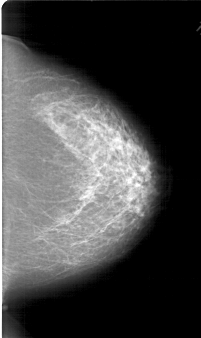

A_1789_1.LEFT_CC

LEFT_CC LINES 6871 PIXELS_PER_LINE 3706 BITS_PER_PIXEL 12 RESOLUTION 43.5 OVERLAY